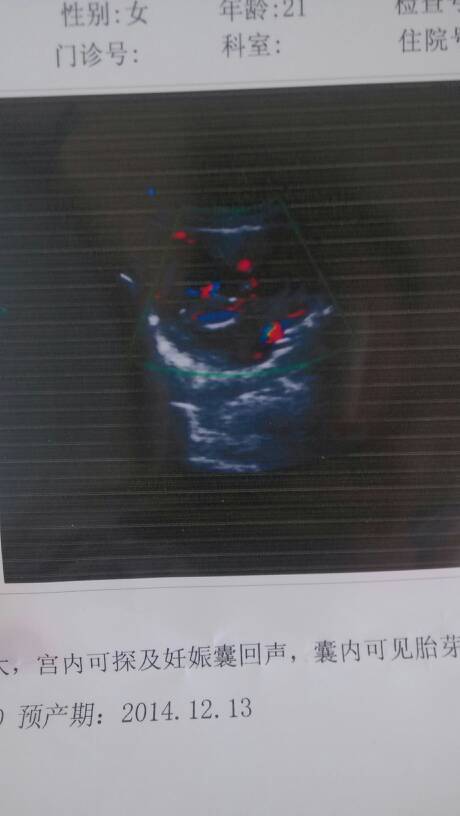

好心的帮忙看看这个 b超有问题吗?我现在怀孕差两天三个月,刚做了个b超也看不懂 好心的帮忙看看这个 b超有问题吗?我现在怀孕差两天三个月,刚做了个b超也看不懂 点击展开 若只如初見 2014-06-04 10:50 为您推荐: 其他回答 上次图片不完整,显示部分没有发现异常情况,建议做好孕期保健工作,结合当地妇科医生看看。 爱狂风一样舞蹈 2014-06-04 20:16 你这是彩超么? 孕妈伤不起 2014-06-04 10:57 相关问题 帮忙看看有问题吗?现在怀孕差两天三个月,自己看不懂! 胎儿顶臀6 2是怀孕几周 5月5号b超的 到现在是多少周了 我忘记了末次月经 我怀孕到现在34周了,就32周时在妇幼保健院孕检了一次,验血,验尿,做了下B超,医生说一切正常 但